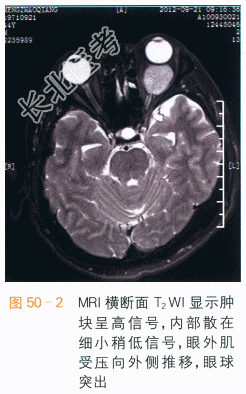

眼眶海绵状血管瘤CT表现为肌锥内类圆形边界清楚之占位,软组织密度,可见结节状钙化,注入造影剂后,呈渐进性强化,为该病的特征表现。肿块占位效应较轻,肿块较大时眼外肌受压向外侧移位,眼球向前方突出。MRI检查时,病灶的T₁WI信号和肌肉类似如图50-1所示,若有血栓形成,可表现为不规则高信号,T₂WI呈类圆形高信号,内偶可见细小低信号分隔,周围假包膜呈低信号,通常没有囊变或坏死如图50-2所示。MRI多平面扫描可以清晰显示肿块的边界,其与视神经、眼球、眼外肌分界清楚,见渐进性强化如图50-3、图50-4所示。